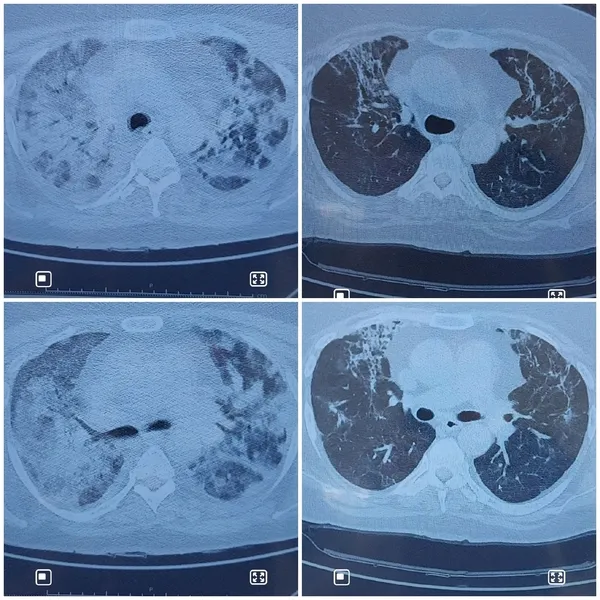

Koronavirüs salgınında hasta ve hasta yakınlarının en büyük tedirginliklerden birinin Faviprivir ve Hidroksiklorokin etken maddeli ilaç olduğunu belirten Prof. Dr. Şevket Özkaya; "Kovid hastalarına önce Hidroksiklorokin ile Favipiravir adli ilaçlar veriliyordu. Hastalar bu ilaçları kullanıp kullanmamakta tereddüt ettiler. Çünkü bu konuda medyada çok olumsuz haber duydular. Kovid- 19 virüsüne karşı spesifik dediğimiz virüsü durduran bir ilaç henüz dünyada yok. Başka hastalıklar için kullanılan mevcut ilaçlardan laboratuar ortamında virüsün hastalık yapmasını önleyen ilaçlar insanlarda kullanıldı. Bu ilaçları zaten insanlar endikasyon olduğunda kullanıyorlardı ama sıtma ilacı Hidroksiklorokin bu virüste etkili olmadığı için tedaviden kaldırıldı. Favipiravir ise aslında başka bir virüste kullanılan ilaç. Favipiravir'in Koronavirüs tedavisinde yararlı ve etkili sonuçlarını gördük. Mesela 54 yasında kadın hastamız Kovid pozitifti ve 13 gün ara ile tam düzelme oldu. Bu Favipiravir, Steroid ve immunplasma tedavisi ile oldu. Bunu bir çok hastamızın kontrollerini yaptığımızda açık bir şekilde görüyoruz" diye konuştu.